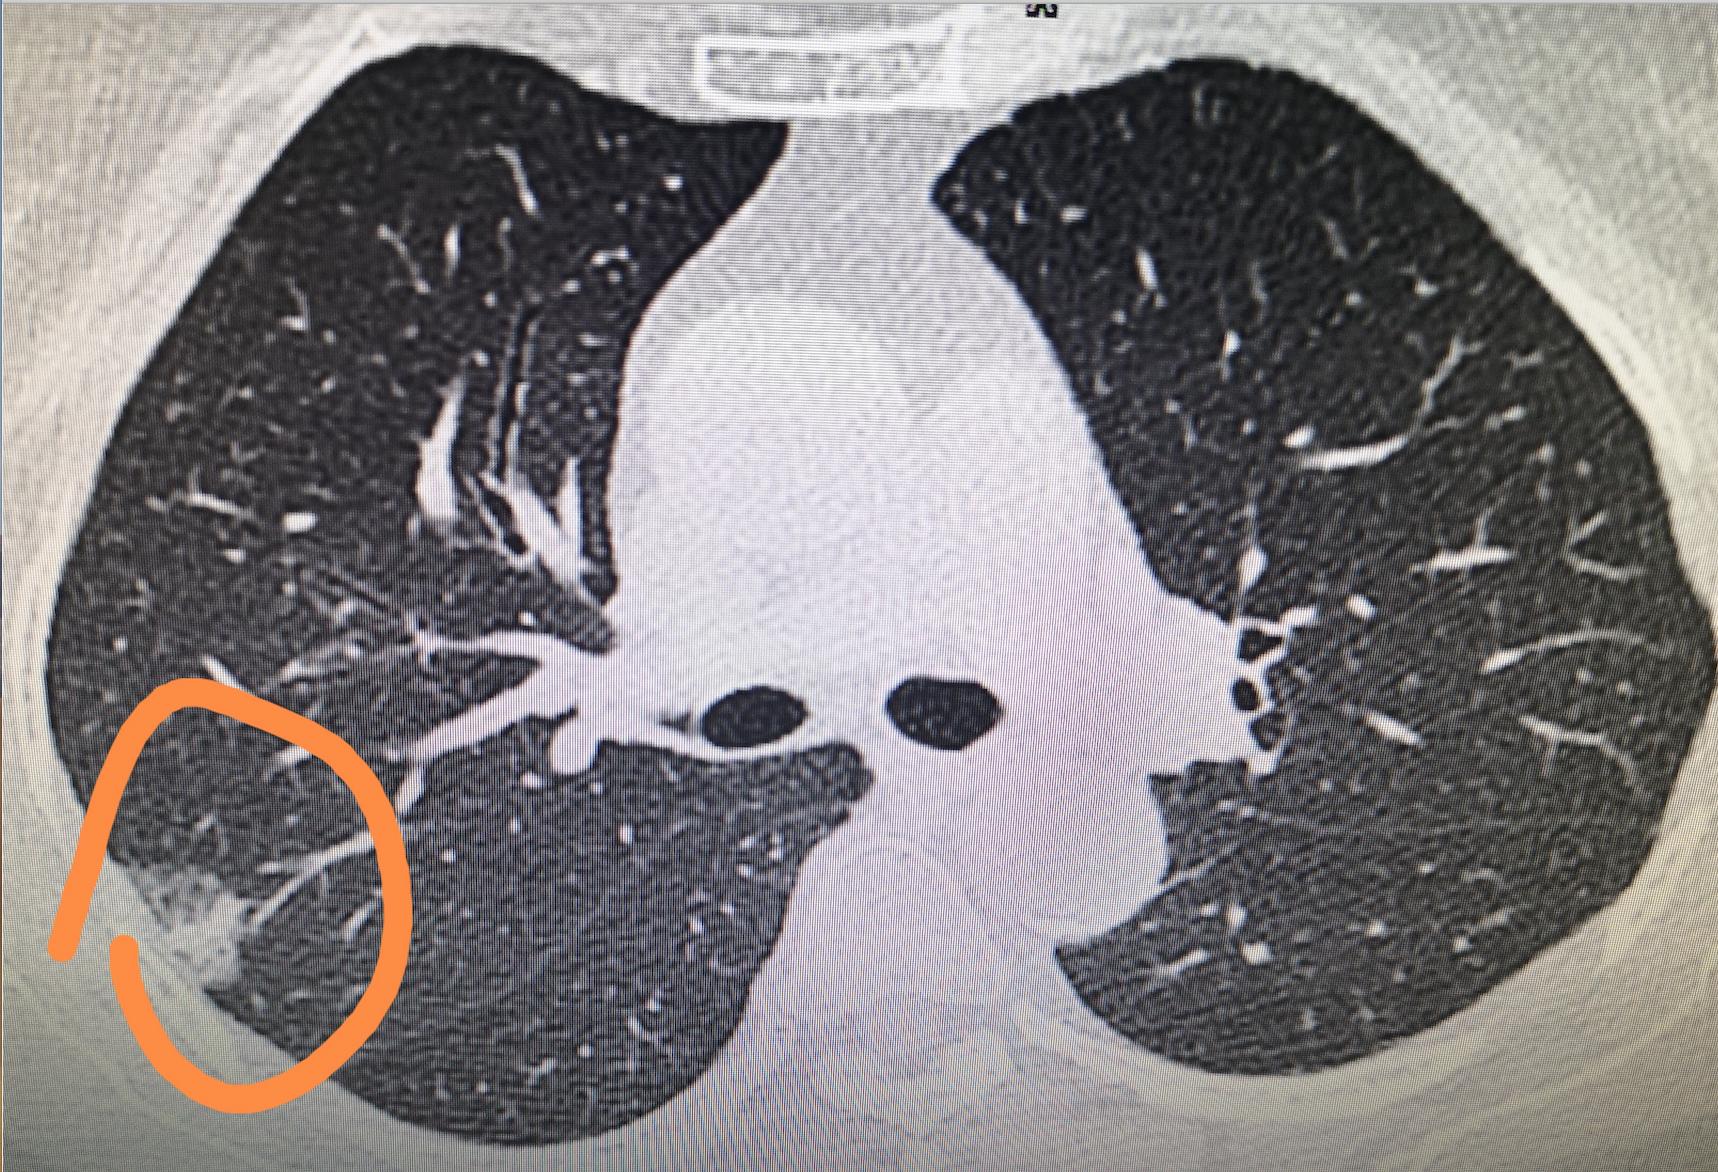

从官方的解释来说,肺磨玻璃结节(GGN)指的是CT影像上,像磨砂玻璃质地的密度轻度增高的云雾状淡薄影。GGN中的磨玻璃成分对应的是病理上的鳞屑样生长方式,异常增生的上皮细胞或分化良好肿瘤细胞以鳞屑样方式生长而形成影像上的磨玻璃影。具体表现为增生的细胞沿现有的结构和肺泡壁生长而不侵犯基质、胸膜或血管,保持完整的肺泡结构,基底膜仅有轻度反应。它打破了恶性肺部肿瘤生长或倍增的“两年定律”,不遵守PET检查SUV值增高的规律,表现为非常明显的惰性生长的特点,直径倍增时间可长达3-5年。

简单点儿来说,肺脏是由许多个肺泡为单位构成的,肺中的支气管经多次反复分枝成无数细支气管,末端膨大成囊,囊的四周有很多突出的小囊泡,这些小囊泡就是肺泡。如果有一群异常增生的上皮细胞或分化良好的肿瘤细胞沿着肺泡壁一直生长,等它长到一定规模时就会在CT检查中被发现,然而胸片却不行。从CT结果的表现来看,就像是在紧密的肺组织上有一块云雾状淡薄影,但它一般不会遮盖住下面的血管边界清晰,此时这群上皮细胞的分裂增殖会比较慢,整体表现出惰性生长的特点,结节直径增长一倍的时间可长达3-5年。

肺磨玻璃结节具有惰性、多样性和演变性的特点,可由良性病变逐步发展成恶性病变,由无侵袭性的惰性病变逐步变成侵袭性的浸润性病变。这个过程可长达几年甚至十几年的时间。在这个程中,病灶逐渐增大,颜色逐渐加深,并由纯磨玻璃成分演变成,磨玻璃成分中出现实性成份。影像学上,可发生从纯GGN→混合型GGN→实性结节的演变;病理学上,发生着从非典型腺瘤增生→原位腺癌→微侵润腺癌→侵润性腺癌(LPA)的演变。